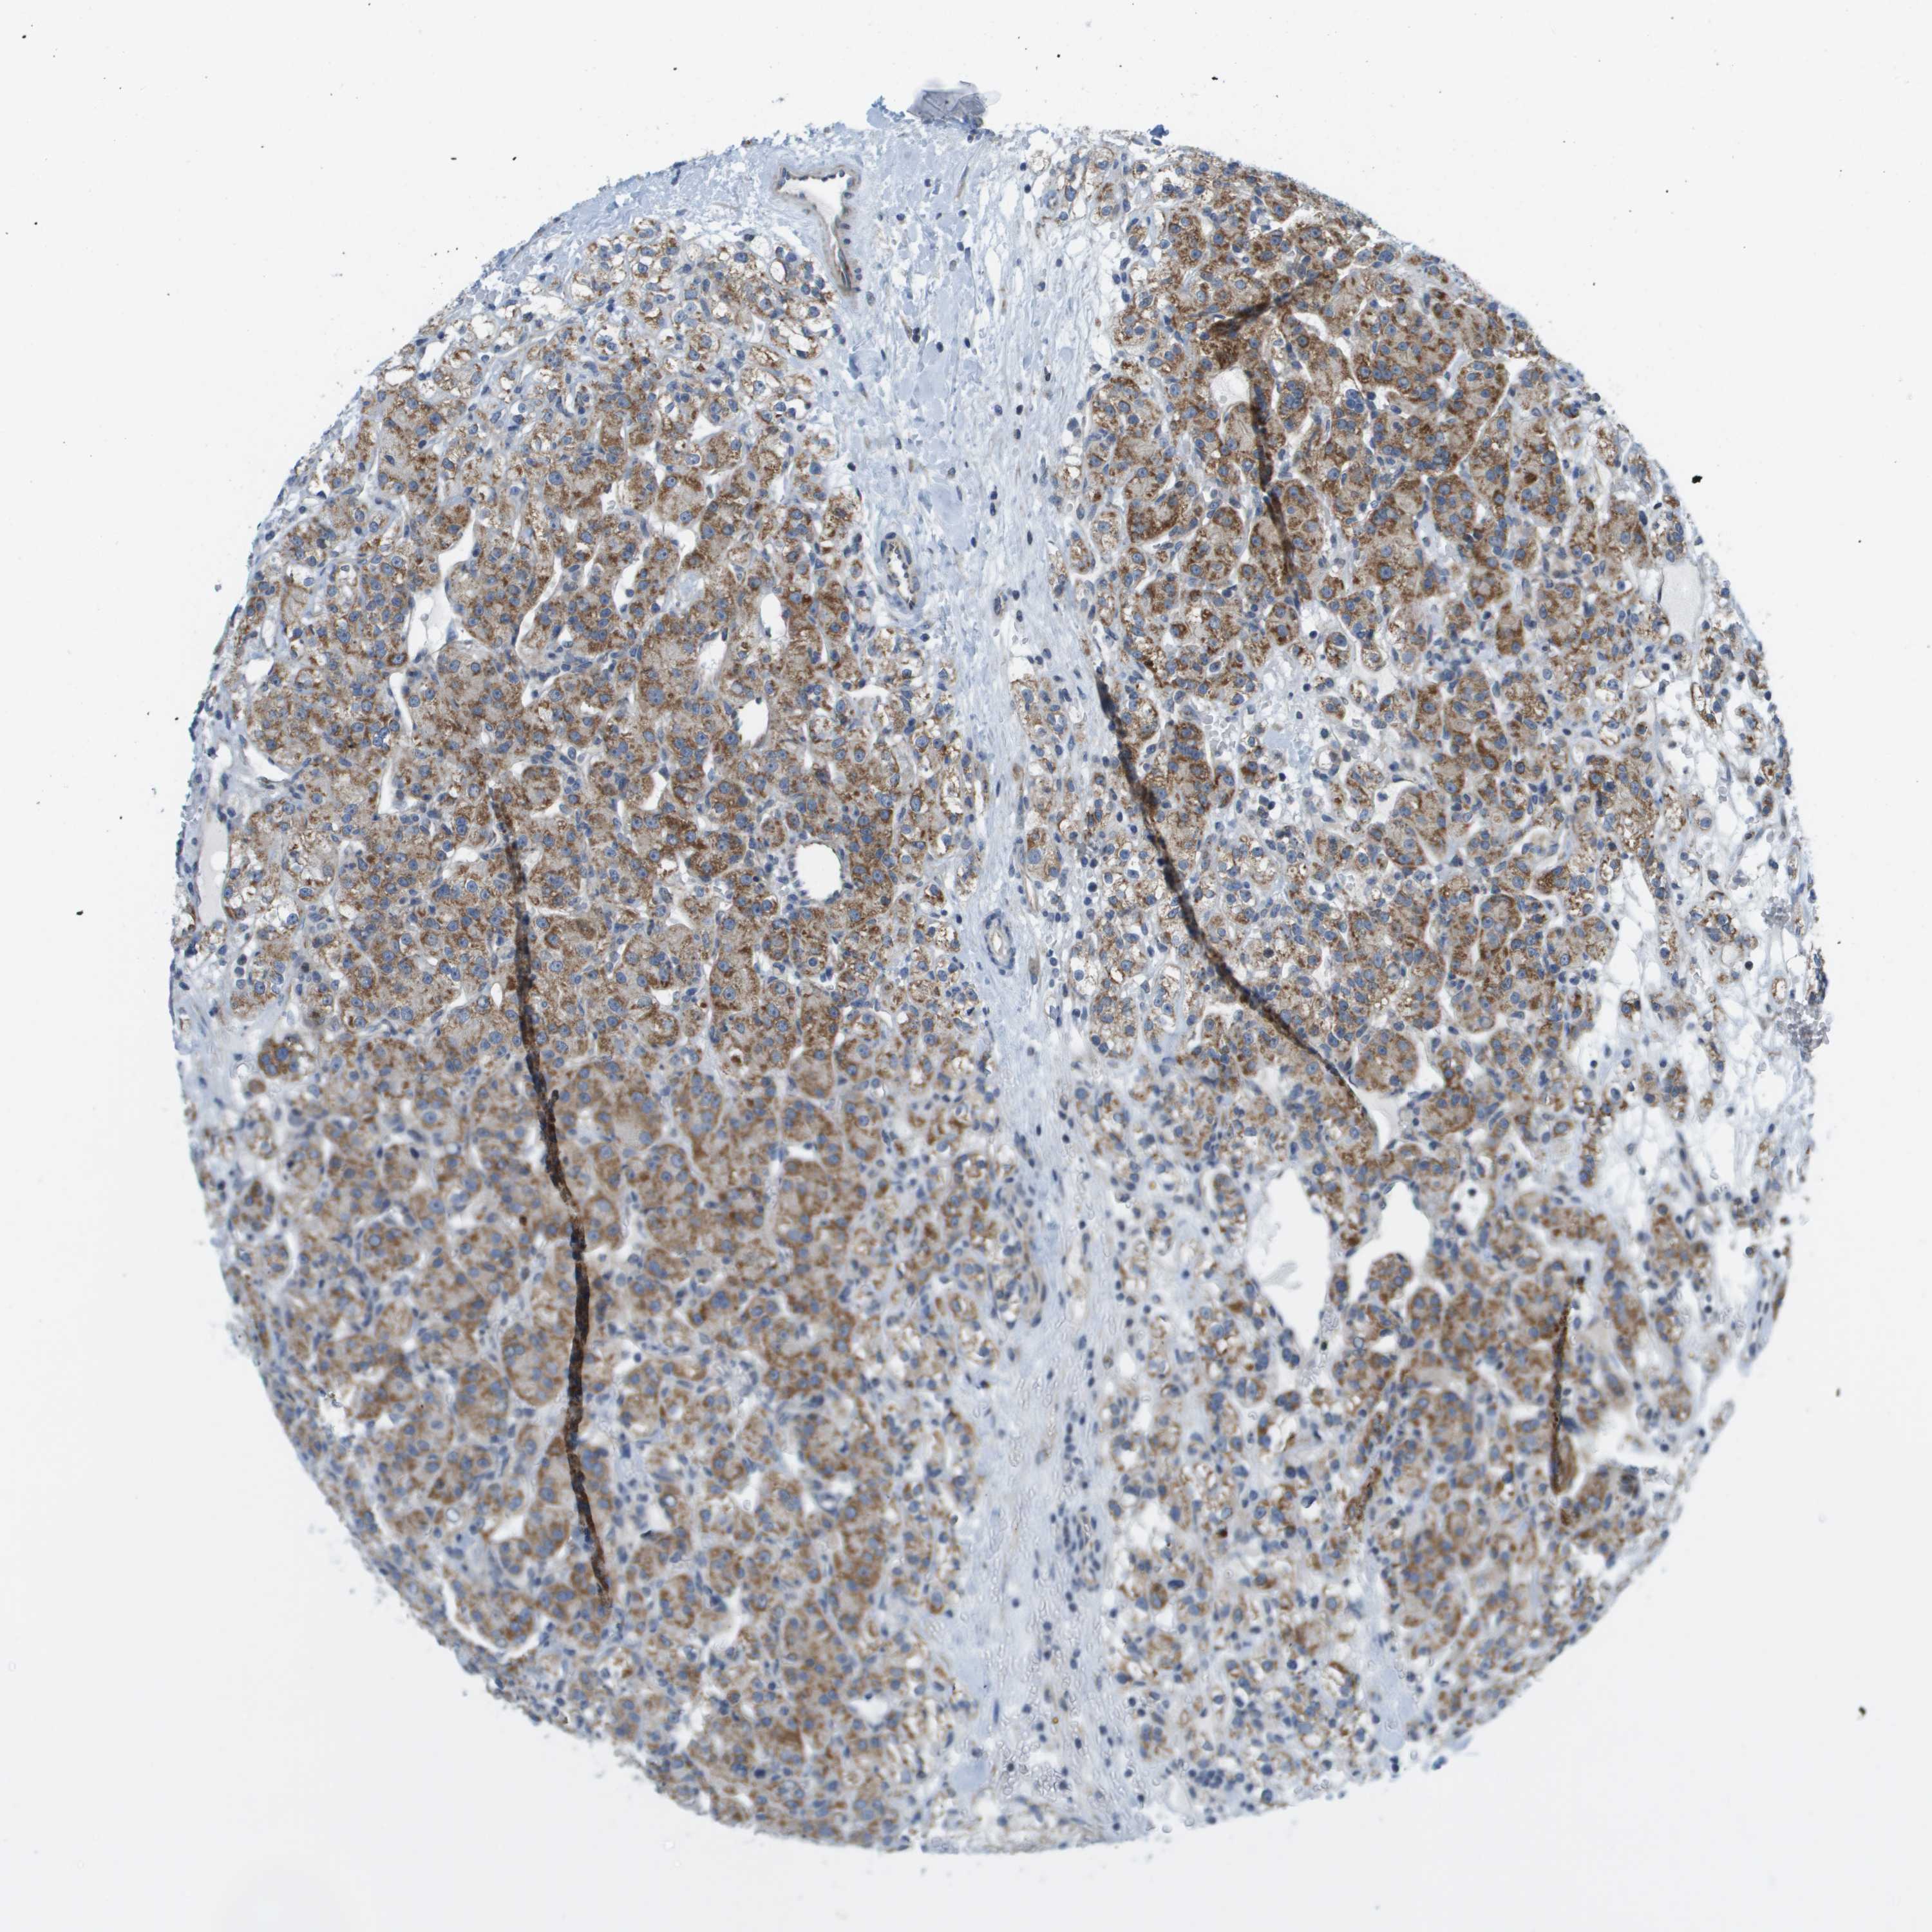

KIDNEY RENAL CLEAR CELL CARCINOMA (VALIDATION) - Interactive survival scatter ploti

The Survival Scatter plot shows the clinical status (i.e. dead or alive) for all individuals in the patient cohort, based on the same data that underlies the corresponding Kaplan-Meier plots. Patients that are alive at last time for follow-up are shown in blue and patients who have died during the study are shown in red.

The x-axis shows the expression levels (FPKM) of the investigated gene in the tumor tissue at the time of diagnosis. The y-axis shows the follow-up time after diagnosis (years). Both axes are complimented with kernel density curves demonstrating the data density over the axes. The top density plot shows the expression levels (FPKM) distribution among dead (red) and alive patients (blue). The right density plot shows the data density of the survived years of dead patients with high and low expression levels respectively, stratified using the cutoff indicated by the vertical dashed line through the Survival Scatter plot. This cutoff is automatically defined based on the FPKM cutoff that minimizes the p-score. The cutoff can be changed by dragging the vertical line or by entering a cutoff value in the square labeled "Current cut-off".

Under the Survival Scatter plot the p-score landscape (black curve; left axis) is shown together with dead median separation (red curve; right axis). Dead median separation is the difference in median mRNA expression between patients who have died with high and low expression, respectively. It is calculated as follows: median FPKM expression of dead patients with high expression - median FPKM expression of dead patients with low expression. This is intended to aid the user in visually exploring custom cutoffs and the associated p-scores and dead median separation.

Individual patient data is displayed and can be filtered by clicking on one or more of the category buttons on the top of the page. Categories describing expression level and patient information include: high, low, alive, dead, female, male and tumor stages. The scale of the x-axis can be toggled between linear and log-scale by clicking on the "x log" button. Mouse-over function shows TCGA ID, patient information and mRNA expression (FPKM) for each patient.

& Survival analysisi

Kaplan-Meier plots summarize results from analysis of correlation between mRNA expression level and patient survival. Patients were divided based on level of expression into one of the two groups "low" (under cut off) or "high" (over cut off). X-axis shows time for survival (years) and y-axis shows the probability of survival, where 1.0 corresponds to 100 percent.

KRT23 is not prognostic in Kidney Renal Clear Cell Carcinoma (validation)

TCGA RNA samplesi

RNA-seq data is reported as average FPKM (number Fragments Per Kilobase of exon per Million reads), generated by the The Cancer Genome Atlas (TCGA) .

Normal distribution across the dataset is visualized with box plots, shown as median and 25th and 75th percentiles. Points are displayed as outliers if they are above or below 1.5 times the interquartile range. FPKM values of the individual samples are presented next to the box plot.

Average pTPM 0.5

Number of samples 100